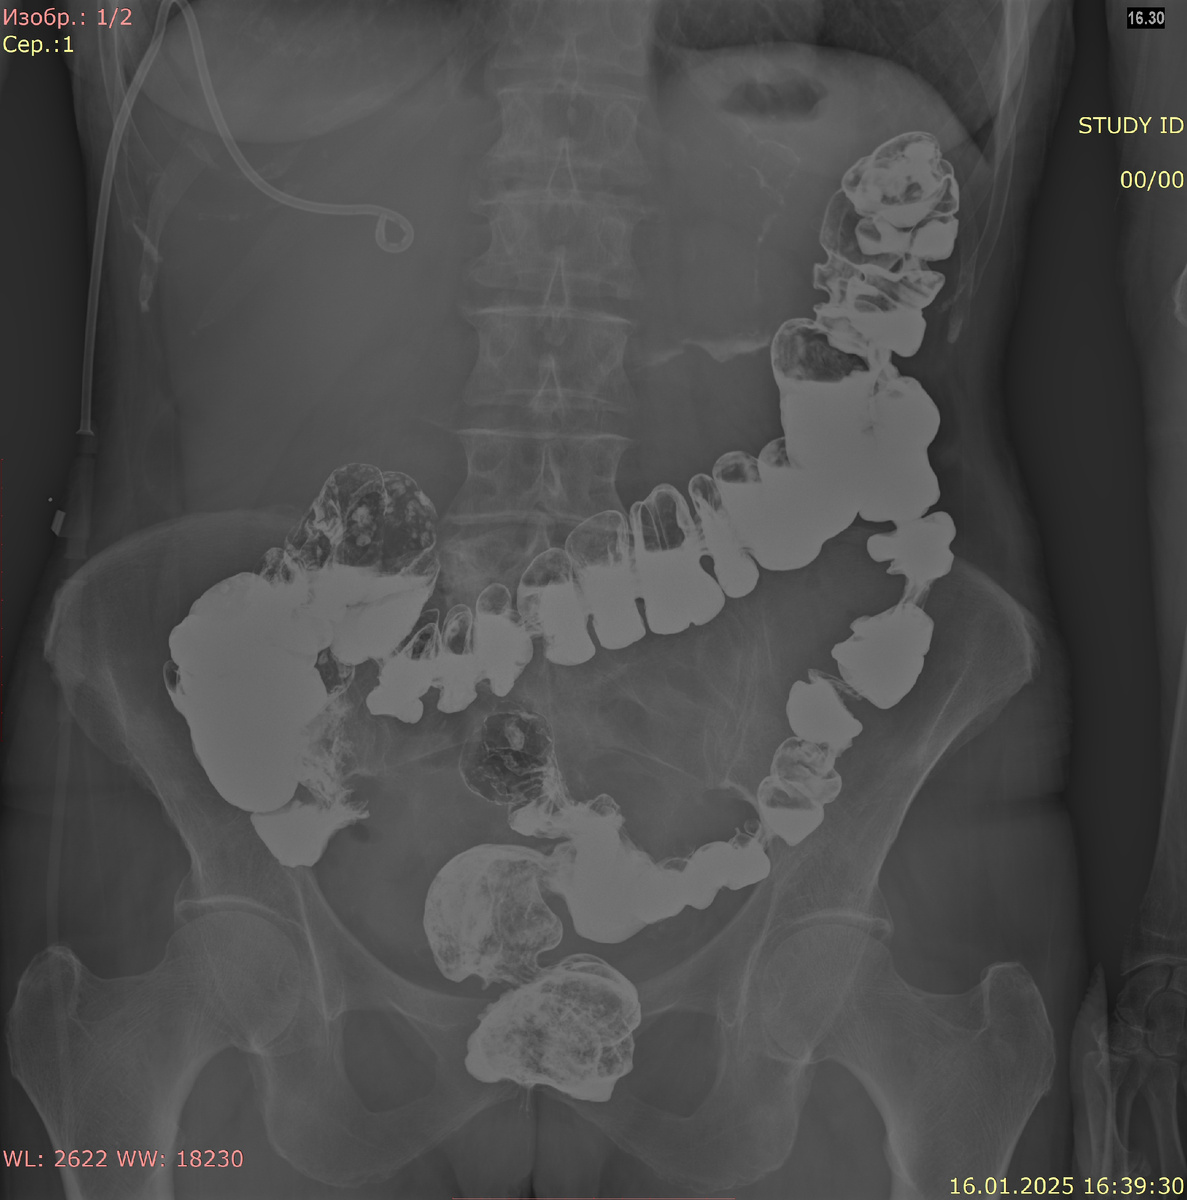

1. Тень кишечника: В норме на снимке живота можно видеть контуры тонкого и толстого кишечника. Тонкая петля кишечника обычно имеет диаметр менее 2,5 см, в то время как толстая петля может быть шире. Излишние или расширенные петли могут указывать на наличие кишечной непроходимости.

Тонкая кишка, состоящая из двенадцатиперстной кишки, тощей и подвздошной кишки, сопровождается характерными изгибами и петлями. Толстый кишечник, в свою очередь, образует «перевернутую U»-образную конфигурацию, находясь по периферии брюшной полости.